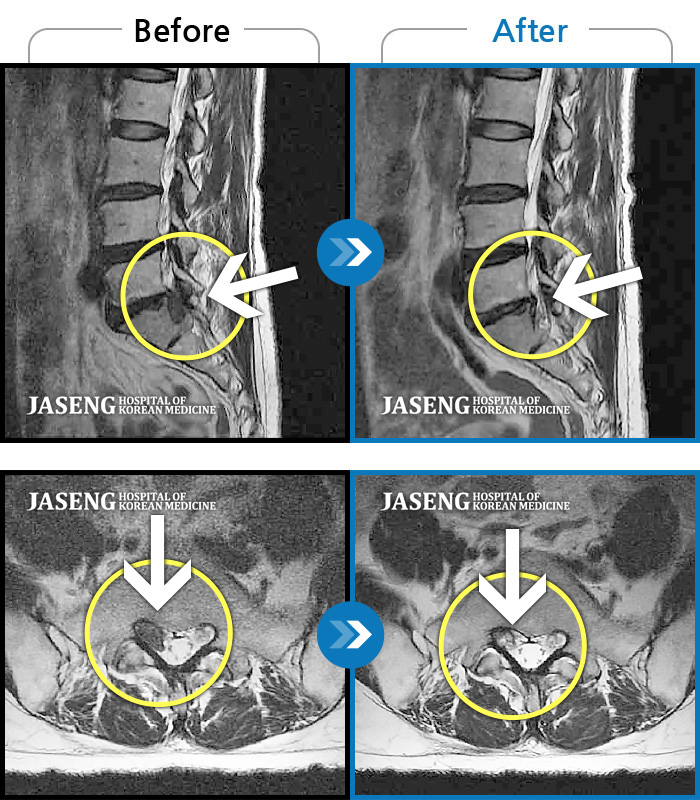

허리디스크

잠실 · 한상욱 원장

허리가 많이 아프고 왼쪽 다리가 저려 움직이기가 힘들다.

촬영시기

2022.01.19 ~ 2022.11.14

2022.12.02